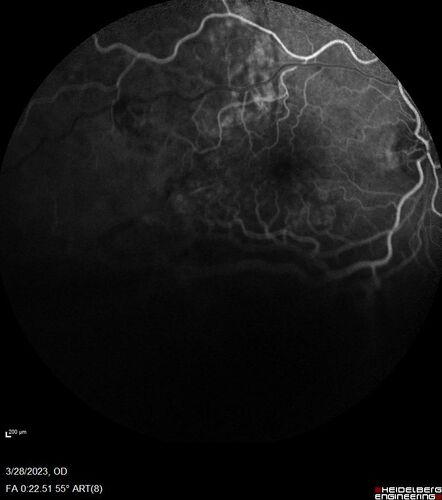

Choroidal Metastatic Breast Cancer with Exudative Detachment

58 year old female presented with 20/200 vision. Had 10 sessions of radiation and tumor shrank. The exudative detachment took almost a year to resolve. The vision improved to 20/40.